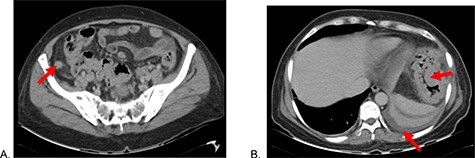

A 51-year-old female patient with a history of uterine polyp treated with curettage 2 years ago and use of omeprazole for gastritis without endoscopic confirmation. A total of 15 days before admission presents mild pain localized in superior hemiabdomen associated with nausea, liquid stools and fever; abdominal pain became diffuse and intensified 2 days before admission, so she goes to emergency room. Physical examination revealed tachycardia, decreased vesicular murmur at base of left hemithorax, slightly distended abdomen, very painful to palpation, positives Mc Burney and rebound signs. Lab test showed significant leukocytosis with left deviation, mild anemia and hypoalbuminemia. The tomography shows thickened cecal appendix, enlarged ileocolic nodes, free fluid around the spleen and splenic flexure of the colon with exophytic tumor (Fig. 1), then diagnostic laparoscopy was decided. A total of 1000 cc of purulent fluid was found throughout the abdominal cavity, thickened cecal appendix but not inflammatory signs, splenic flexure of colon with an inflammatory-appearing tumor with abundant fibrin and multiple paracolic nodes, so laparotomy was decided. During the intestinal section evidenced colorectal mucosa with multiple polyps (Fig. 2), we performed total colectomy and terminal ileostomy for probable familial adenomatous polyposis, patient progresses favorably, is discharged from surgery and referred to medical oncology for management.

Abdominal tomography: (A) Thickened cecal appendix and (B) Perisplenic free fluid, splenic flexure of the colon with exophytic tumor.